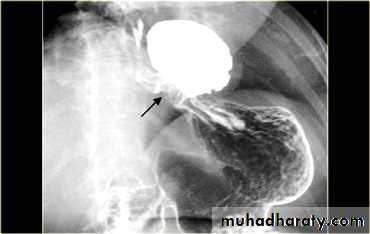

DILATATION (Sac like in proximal part )

Undulating or spiky out line due to sluggish peristalsis.

Non- homogeneity of Barium due to food particles.

Air Barium level.

CXR shows widening of mediastinum.

Absence of fundal gas shadow.

Basal fibrosis in lungs due to repeated aspiration pneumonia .

LEFT: Dilated esophagus (arrows) appears as long, well-defined structure paralleling heart RIGHT: Dilated esophagus usually deviates to right. Narrowing (arrow) at hiatus.

LEFT: CT shows dilated esophagus (arrow) that led to esophagram.RIGHT: Esophagram shows narrowing (arrow) at level of hiatus.